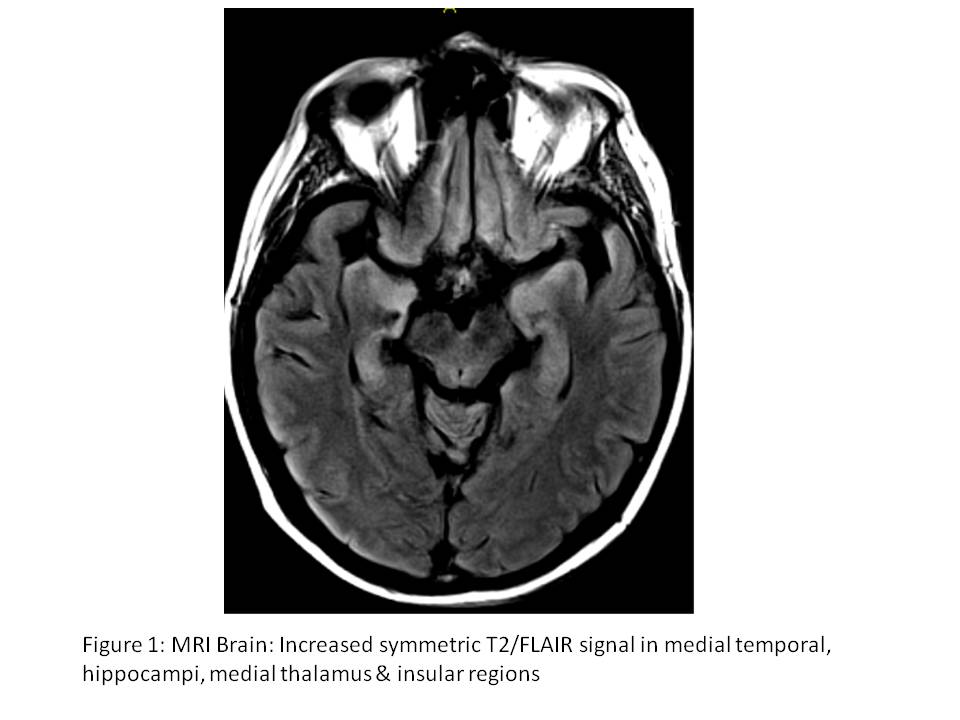

Status Epilepticus Due to Severe HHV-6 Encephalitis in an Allogeneic Stem Cell Transplant Recipient